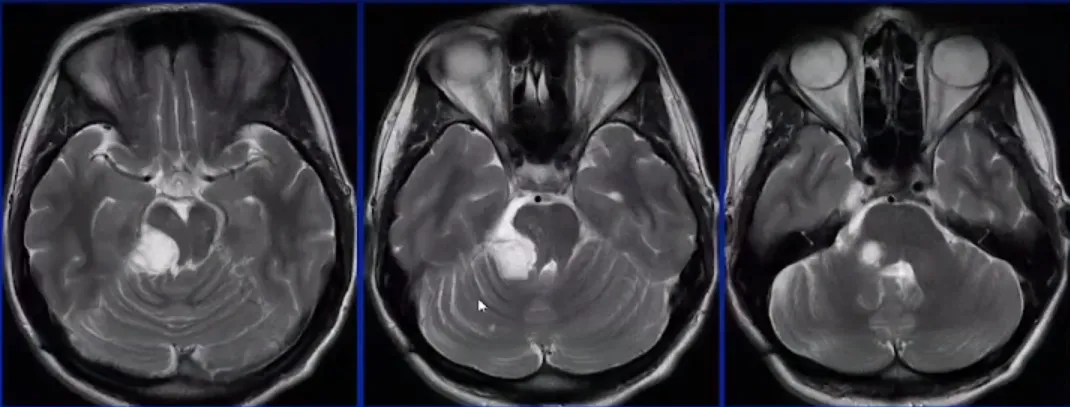

术后MRI

为了达到肿瘤的边边角角,术中需要采用30度、45度乃至70度内镜配合多角度专用器械实施切除。

该案例来自于施罗德教授《Endoscope-assisted mircosurgery in the Posterior fossa》演讲分享。